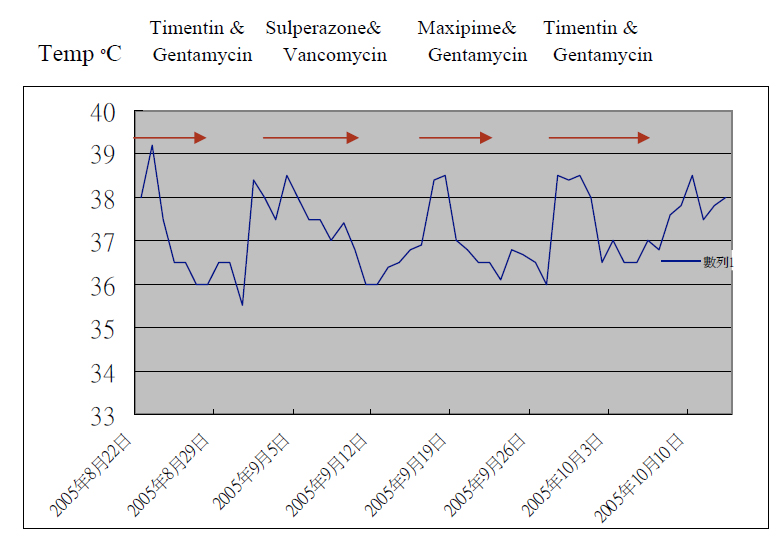

His white cell count was 14.3×109 /L with 14.3% neutrophils and 32.3% lymphocytes. His hemoglobin level was 12.4g/dL. He had normal renal function and normal liver function except mildly elevated ALP of 184 U/L. HBsAg and HCV Ab were negative. His globulin level was 32 g/L. Fasting glucose was 4.5mmol/L. Repeated sputum culture grew Pseudomonas aeruginosa and was resistant to ciprofloxacin. Mid-stream urine and blood culture were negative. Fever was down and clinical and radiological (Fig.2) improved with Timentin and Gentamycin. However, patient developed recurrent episodes of fever and purulent sputum once antibiotics stopped. (Fig.3)

Fig 3. Temperature Chart